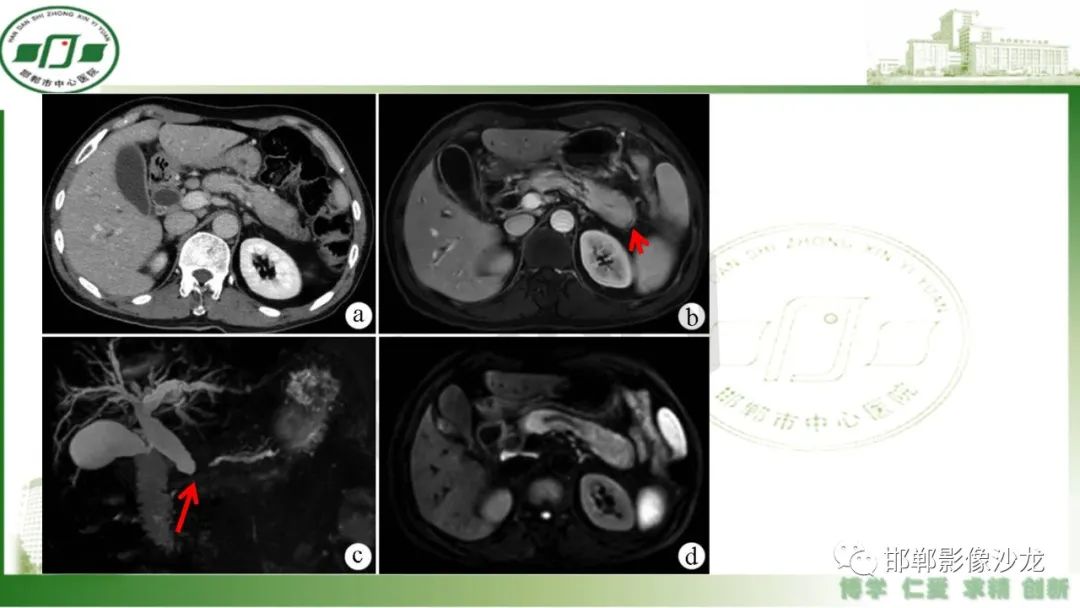

肿块性胰腺炎与胰腺癌的临床、实验室检查、影像学表现有时候很难鉴别,但两者的临床处理、预后又有很大的不同,因此我们平时工作中需要注意两者之间的区别,谨慎诊断,力争为患者及临床带来更大的帮助。